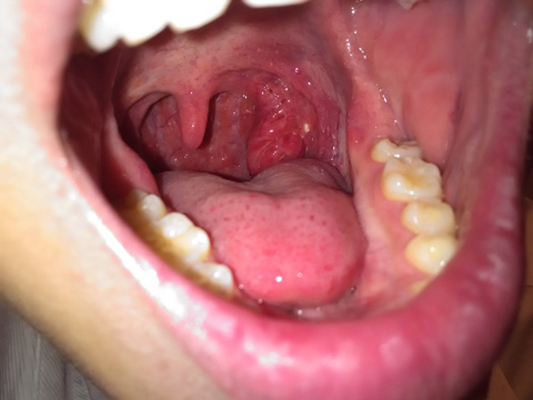

扁桃體週膿腫圖片